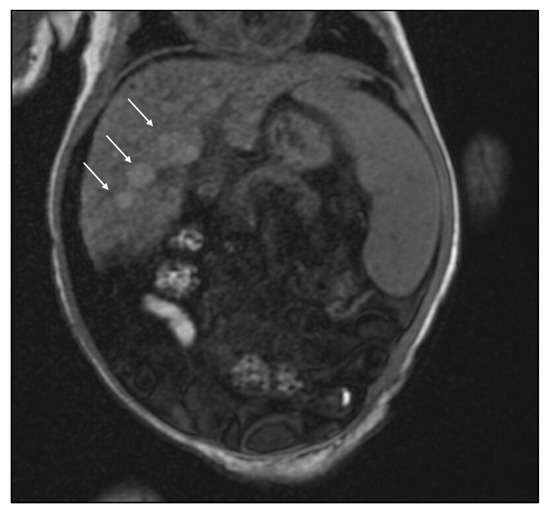

2. Case Report